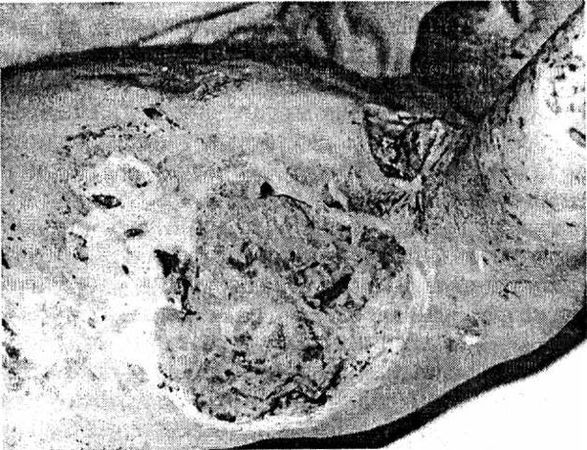

Отмечается следующая последовательность процессов заживления гнойных ран. Вначале происходит очищение очага воспаления от всех некротизированных клеток, тканей, сгустков крови и т. д. После этого на отдельных участках стенок гнойной полости появляются разрастания клеток в виде красных узелков, которые, постепенно увеличиваясь в количестве и размерах, покрывают все стенки и дно раны. Эти красные узелки состоят из молодых соединительных клеток (фибробластов) и называются грануляционной тканью, которая заполняет всю полость гнойного очага до поверхности кожи (рис. 1). После этого кожный эпителий, разрастаясь, покрывает грануляции, клетки которой (фибробласты) постепенно образуют волокнистую соединительную ткань – так образуется рубец.

Рис. 1. Обширные гранулирующие раны грудной клетки